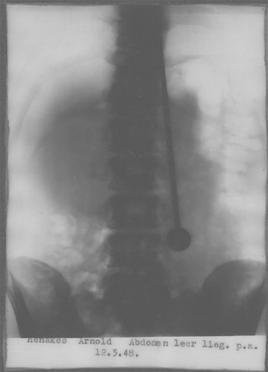

Để kiểm chứng bản thân không sử dụng kỹ xảo, Mirin Dajo đồng ý cho các bác sĩ tiến hành kiểm tra, trong đó có việc chụp X-quang ngay tại hiện trường. Kết quả kiểm tra cho thấy Mirin Dajo thực sự bị dao, kiếm đâm xuyên qua cơ thể.